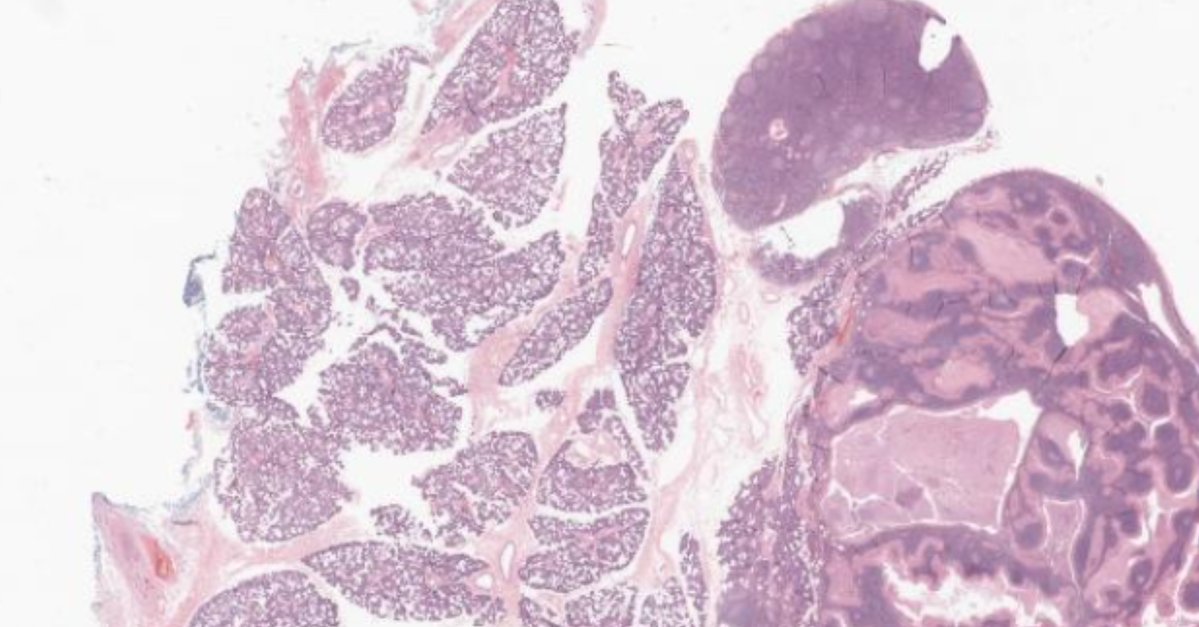

This month’s case features a classic clinical scenario: a painless lesion in the tail of the parotid gland, followed by excision and histologic analysis. Can you pinpoint the most accurate diagnostic insight? Case by Sara Niyazi, MD: https://t.co/4zj6neKDG6